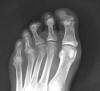

ACT Prótesis de hallux en artrosis.

ACT Prótesis de hallux. Perfil.